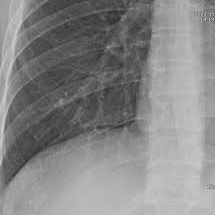

갈비뼈에 금이 가거나 골절이 생기면 생각보다 일상 불편이 큽니다. 팔이나 다리처럼 깁스를 해서 완전히 고정할 수 있는 부위가 아니기 때문에, 통증을 버티면서 숨 쉬고 기침하고 잠자는 모든 과정이 힘들어질 수 있습니다. 특히 갈비뼈 손상은 단순히 “시간이 지나면 낫는다”로 끝나는 문제가 아니라, 통증 조절이 제대로 되지 않으면 깊게 숨을 쉬지 못해 폐 합병증 위험까지 커질 수 있다는 점이 중요합니다. 실제로 갈비뼈 손상은 대부분 자연 치유가 가능하지만, 회복 속도를 좌우하는 핵심은 무리한 민간요법보다 통증 관리, 호흡 유지, 적절한 활동 조절, 균형 잡힌 영양 섭취에 있습니다.

대체로 수주 내 호전되는 경우가 많지만, 통증이 심하거나 호흡곤란, 발열, 피 섞인 가래, 흉부 압박감이 동반되면 단순 타박상이나 금이 간 수준이 아니라 추가 평가가 필요한 상황일 수 있습니다.

갈비뼈에 금이 가면 가장 먼저 나타나는 것은 국소적인 통증입니다. 가만히 있을 때보다 몸을 비틀거나, 기침하거나, 재채기하거나, 깊게 숨을 들이마실 때 통증이 확연히 심해지는 경우가 많습니다. 눌렀을 때 특정 부위가 유난히 아프고, 자세를 바꾸거나 침대에서 일어날 때 찌르는 듯한 통증이 반복되면 갈비뼈 손상을 의심할 수 있습니다. 피부 멍, 압통, 붓기, 드물게는 ‘딱’ 하는 느낌이나 소리를 경험하는 사람도 있습니다. 다만 증상만으로 단순 타박상과 미세 골절을 완전히 구분하기는 어렵고, 외상 강도가 컸거나 고령자, 기저 폐질환자, 골다공증 위험군이라면 더 신중하게 봐야 합니다.